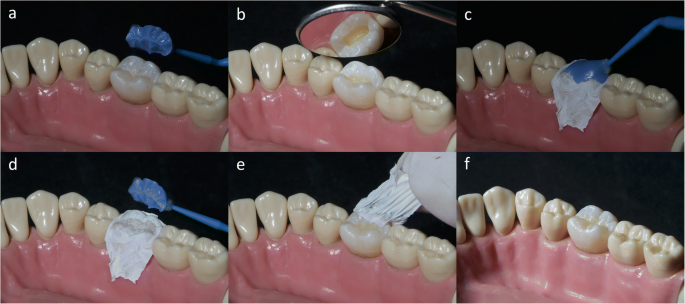

✦ 마이크로 브러쉬 (이덴트)

✦ 퀵스 플로우 (플로워블 임시충전재 아무거나)

✦ (의료용) 테플론 테이프

✦ 피슈라 레진 어플리케이터

사진은 이덴트에서 떼온거구요,

✦ 마이크로 브러쉬를 살짝 얹고

퀵스를 좀 더 짜서 브러쉬를 덮어줍니다.

그리고 광중합을 한 뒤 떼어내면

교합면의 pit and fissure가

퀵스에 인상이 돼서 나오겠죠?

그걸 나중에 패커블레진에 찍어서

교두경사를 재현하는 테크닉이에요.

그러니까 패커블 레진을 일단

와동을 채울 정도로 잘 적용해놓고

✦ 그 위에 '테플론 테이프'를 덮은 다음

스탬프를 찍어야해요.

그리고 테이프를 살살 떼어낸 다음

✦ 피슈라를 이용해서

와동 바깥으로 밀려나온 레진을

떼어내준 다음에 광중합하세요.

✦ 그래서 애초에 마이크로 브러쉬를 안쓰고

메탈 스토퍼를 이용해서 할 수도 있어요.

구강 내에 엄지를 넣어서

스탬프를 꾹 눌러주시거나

최소한 핀셋이나 스타퍼등

스티프한 기구를 이용해서

스탬프가 잘 찍히도록 강하게 눌러주세요